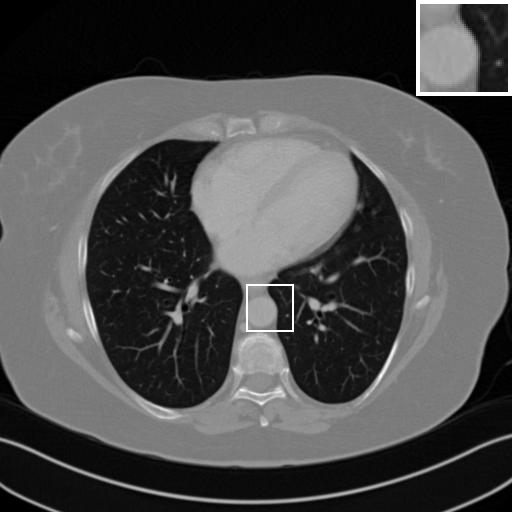

Fig. 4 presents the reconstruction results and residual images obtained by different methods for limited-angle reconstruction. As can be seen, the learning-based methods outperform the direct method and TV model, which exhibit serious artifacts in the missing angle region. Although the denoiser introduced by the FBP-Unet can somehow deal with the noises, the result still presents obvious artifacts. Compared to the SIPID, PD-net and FSR-nets, our LRIP-net1/2 can better preserve the image details and edges with less information left in the residual images. Thus, both the quantitative and qualitative results confirm that the low-to-high double-resolution strategy can improve the reconstruction accuracy for the limited-angle reconstruction problem.

We observe that the low-resolution image prior plays an important role in our method. More specifically, we compare the results of our LRIP-net with respect to different low-resolution priors, which are obtained by down-sampling rate of 1/2, 1/4, and 1/8, respectively. As can be seen in Table III, the best reconstruction results are obtained with the image prior reconstructed by the down-sampling rate of for 150∘, 120∘ and 90∘ limited-angle reconstruction. The visual comparison based on different image priors are also provided in Fig. 5, where obviously less artifacts are left in the reconstruction image by LRIP-net1/8. By comparing the running time, it is easy to see that the smaller the low-resolution image prior, the faster the LRIP-net works.